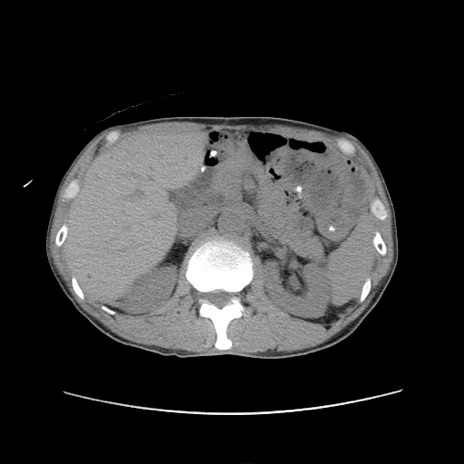

冠状断像

症例11(横断像)

【症例】 60歳代男性

【主訴】 下腹部痛

【現病歴】 本日夜中より下腹部痛の症状認め、受診。

【既往歴】 膀胱癌(膀胱全摘+尿管皮膚瘻術) 、胃癌術後

【身体所見】 BT 35.3℃、PR 58/min、BP 136/98mHg、腹部平坦、軟、腸蠕動音±、ストマ留置あり、左上腹部~正中部に圧痛あり、反跳痛なし。

【データ】WBC 5100、CRP0.01